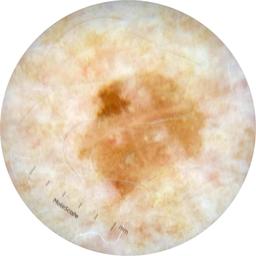

ISIC_8490164

Field Value

acquisition_day 218

age_approx 65

anatom_site_1 Upper extremity

anatom_site_general upper extremity

concomitant_biopsy False

diagnosis_1 Benign

diagnosis_confirm_type single image expert consensus

family_hx_mm True

fitzpatrick_skin_type I

image_manipulation instrument only

image_type dermoscopic

lesion_id IL_9551927

patient_id IP_2259625

personal_hx_mm True

sex female